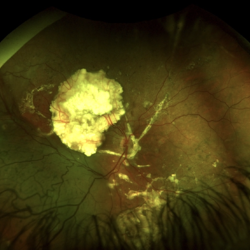

Cavernous Hemangioma

Fundus photograph of a 44-year-old woman with a cavernous hemangioma

Imaging device: Optos California

Condition/keywords: cavernous hemangioma